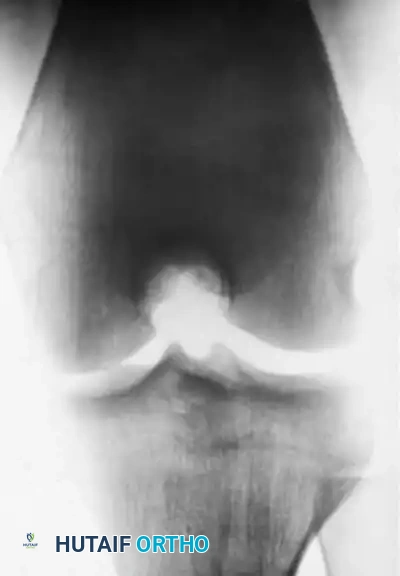

Image

As demonstrated in the clinical case above, an adolescent with an open physis and a stable lesion was treated nonoperatively in a cast for 9 months. Several years later, complete radiographic healing is apparent, and the knee is entirely asymptomatic. However, prolonged immobilization must be balanced against the risks of muscle atrophy and joint stiffness. Contemporary protocols favor hinged knee braces and strict cessation of sports rather than rigid casting.